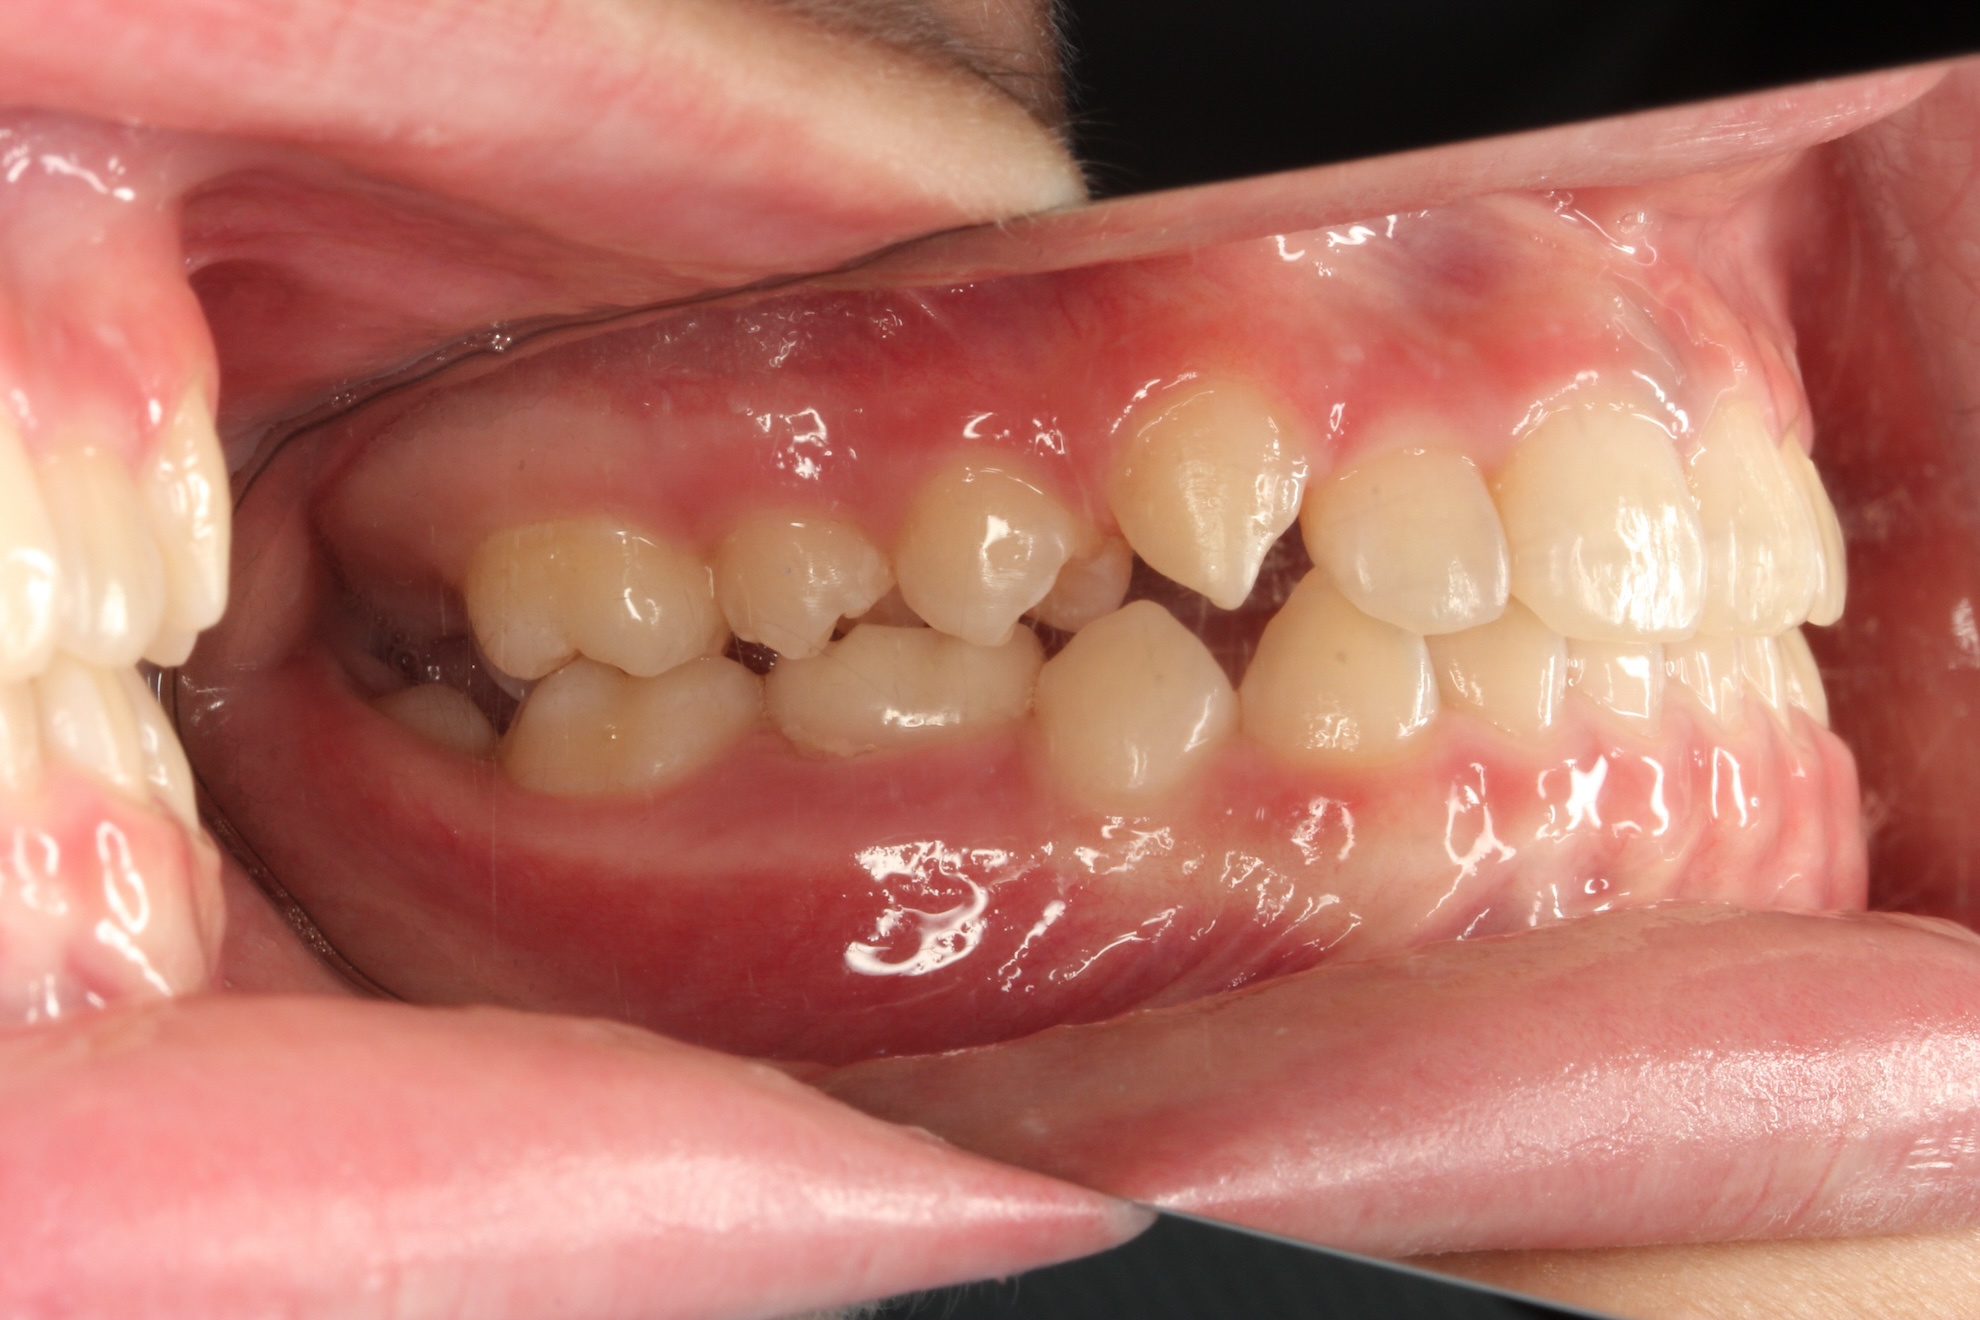

反対咬合(受け口)を改善しました

BEFORE

反対咬合の治療前

AFTER

反対咬合の治療後

年代・性別

8歳 男の子

主訴

上下反対の噛み合わせを治したい

診断

骨格性Ⅰ級、歯性Ⅲ級、機能性反対咬合

治療内容

アクティブプレート、部分的な唇側ワイヤー矯正、リテーナー

治療期間

3年

治療リスク

痛み、歯根吸収、歯肉退縮

治療費用

約40万円